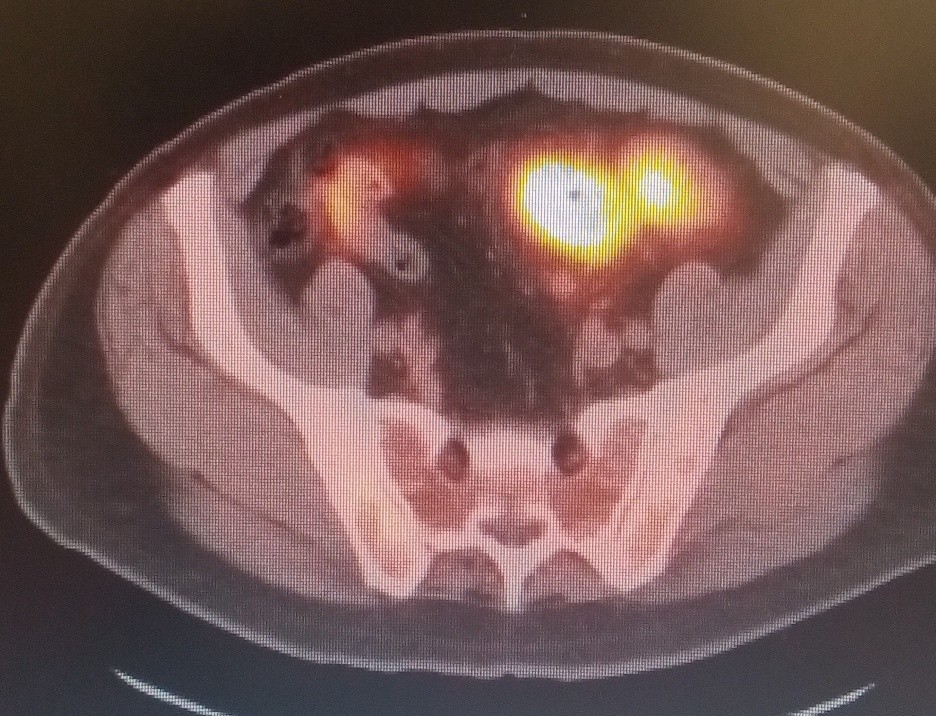

The patient is a 59-year-old male who was accidentally found to have liver lesions when he underwent (CTA) computed tomography angiography for chest pain (Figure 1). A subsequent positron emission tomography scan (PET) revealed metastatic disease in the liver (Figure 2), most likely originating from the primary sigmoid colon cancer (Figure 3). CT-guided liver biopsy of the liver lesion confirmed metastatic disease with histologic features consistent with a primary of colorectal origin. His blood test showed elevated colonic embryogenic antigen (CEA) of 38 ng/ml.

Figure 2. PET scan showing multiple Liver metastasis

Figure 3. PET scan showing primary source of malignancy in sigmoid colon

Figure 2

Figure 3